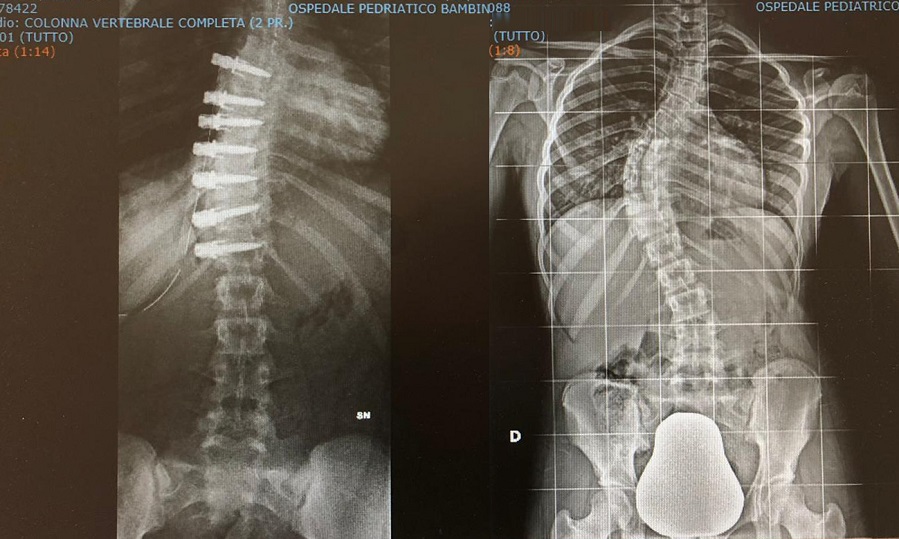

La scoliosi adolescenziale idiopatica è una curvatura laterale della colonna vertebrale che si sviluppa durante l’adolescenza senza una causa chiara. In alcuni casi, quando la curvatura raggiunge un grado significativo e si prevede che possa progredire, si può considerare la fusione lombare posteriore.

La fusione lombare posteriore è un intervento chirurgico che mira a correggere la curvatura e stabilizzare la colonna vertebrale. Durante l’operazione, le vertebre interessate vengono fuse insieme utilizzando viti, aste e innesti ossei.